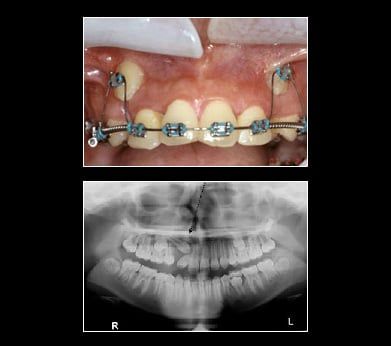

Ectopic canines are generally found in the Buccal Vestibule. Impacted canines may be retrieved with braces, using a surgical approach via a gold chain or straight wire. Tissue covering the tooth is uncovered. A chain or wire is attached to the tooth crown. Tissue is placed back over the tooth leaving the chain or wire coming out of the gum. For the purpose of this illustration a gold chain is used to retrieve the canines. The chain is attached to the tooth crown and the link is attached to a flexible archwire so that the wire is active (bent). Once a month, the wire is reactivated by using the next link up on the chain until the impacted canine erupts enough to attach a regular bracket on the canine. With the regular bracket in place, a more flexible wire is added directly to the bracketed canine. This process will bring the canine into position within the arch by forcing the canine to conform to the straight archwire form. This is a long process taking anywhere from 8-12 months.